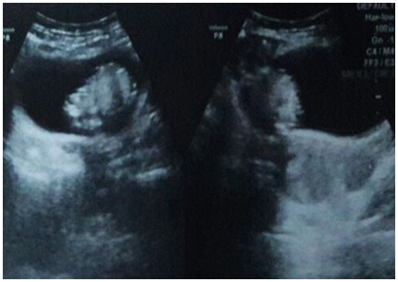

There was a pelvic ultrasound done by a local sonologist which reported a mass in the urinary bladder with normally visualized both ovaries & uterus. The scan was repeated and revealed an intra vesicular echogenic mass (Figure 2) with normal right ovary and uterus. However; left ovary was not visualized. Due to non visualization of the Ovary, the patient was advised to get a pelvic MRI, which revealed a mixed intensity lobulated well defined mass along the dome of the Urinary bladder with both intra & supra vesicular components (Figure 3). There were internal T1 hyper intense areas showing low intensity on fat suppression and a focus of signal void; suggesting internal fat and calcific intensities, respectively. Few small cyst like foci (follicles) could be visualized in the supra vesicular component of the mass with non visualized separate left ovary. Right ovary and Uterus were normal. Diagnosis of Left Ovarian dermoid cyst with cysto-vesical fistula was made. In view of academic interest and for diagnostic correlation, pelvic CT scan was acquired; under complete patient satisfaction and informed consent (Figure 4).

Figure 2 Pelvic trans abdominal ultrasound image showing echogenic mass in the urinary bladder lumen with normal uterus.